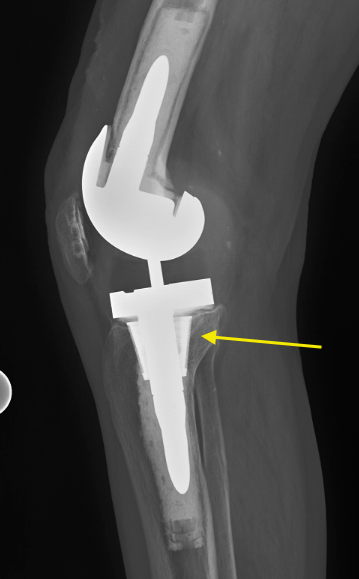

Once the guide and the template are in place, the cavity is prepared by cutting at a trajectory that mills or reams the bone to exactly match the shape of the implant. Since cones achieve their stability through press-fit, a good seating of the cone in the bone (Figure 2) is paramount for primary stability, which is the basis for osseointegration (Figure 3).